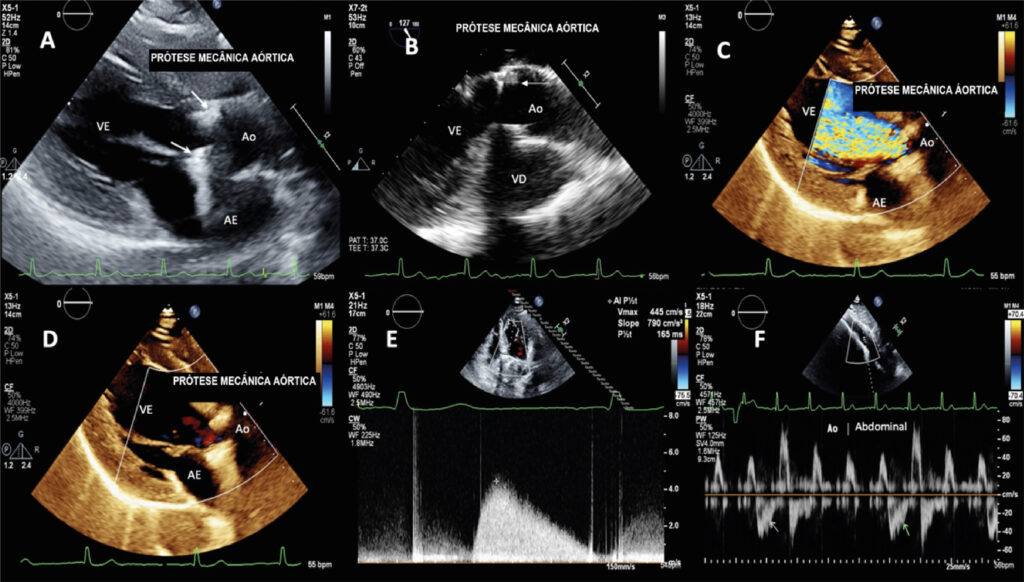

Intermittent mechanical prosthesis dysfunction is a rare and potentially serious complication1 – 4 that can affect prostheses in the aortic5 or mitral position. It causes obstruction or intermittent central regurgitation depending on the phase of the cardiac cycle in which the disk becomes stuck.3 The most common cause of this dysfunction is pannus formation,3 , 4 which may also occur due to thrombosis, mitral subvalvular tissue, suture material, vegetations, ventricular myocardium,3 or mechanical failure.2 Left untreated, transient mobility loss leads to permanent disk immobilization.3 In this scenario, a patient in whom a size 21 Carbomedics® metallic aortic prosthesis was implanted 14 years prior was referred for echocardiography due to abnormal cardiac auscultation findings. Transthoracic and transesophageal echocardiograms showed significant intermittent central prosthetic regurgitant jet unrelated to arrhythmias ( Figure 1 ; Videos 1 and 2 ). The mean prosthetic gradient was 29 mm Hg and the effective valve area was 1.08 cm². A refringent, periannular, fixed, sub- and supra-prosthetic image suggestive of pannus was also identified (Figure 2), which became the main etiological hypothesis for this unusual dysfunction presentation.